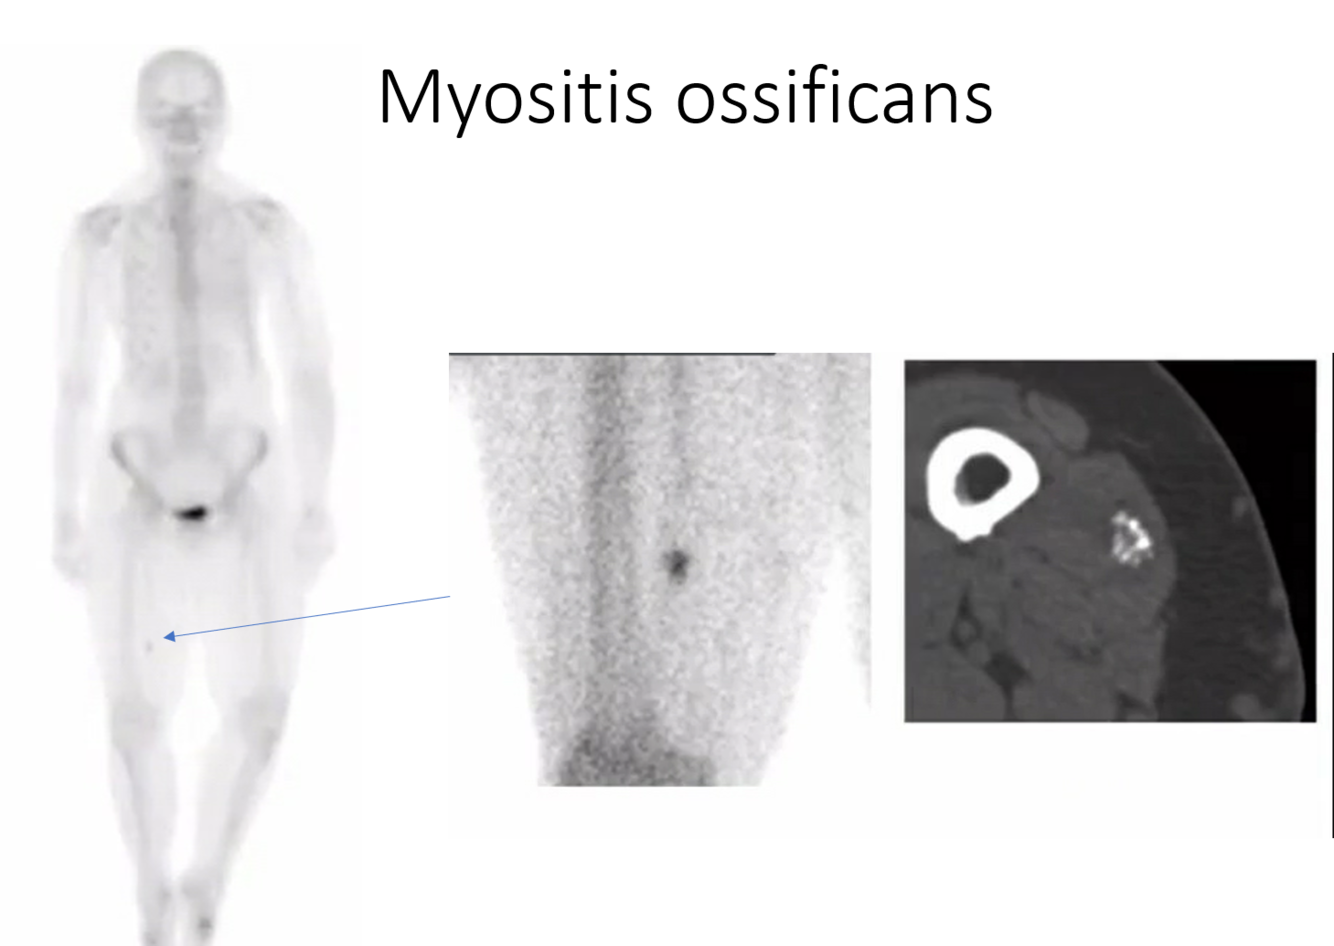

Soccer player with lots of trauma to the thigh. Next step?

get more imaging - CT or XR to further evaluate possible myositis ossifcans